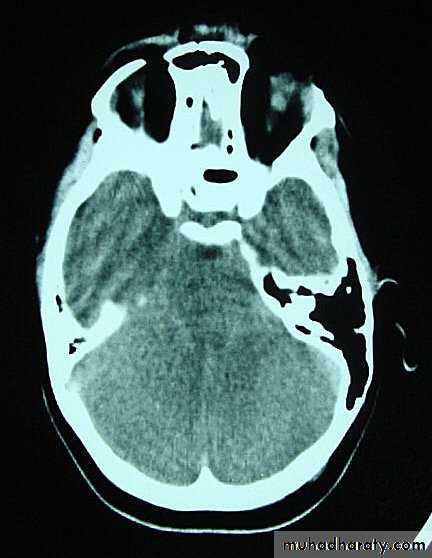

b. Subdural Haematoma

They are the most common intracranial mass lesions resulting from head trauma.

They are classified depending on how long they take to present clinically following the injury into:

Acute Subdural Haematoma: less than 3 days

Subacute Subdural Haematoma: 4-21 days

Chronic Subdural Haematoma more than 21 days.

Chronic Subdural Haematoma

Most common in infants and in adults over 60 years of age secondary to SLIGHT blow to the head which may pass unnoticed.

Source of bleeding (haematoma): usually from bridging veins as they pass to the venous sinuses.

The patients present with progressive neurological deficits more than 3 weeks after the trauma.

The initial head injury is often completely forgotten.

CT scan: the acute clotted blood is initially appears white (hyperdence), but as it liquefies, it slowly becomes black (hypodense).

They should be drained if they continue to enlarge.

They are evacuated by drilling burrholes over the collection and washing it out with warmed saline.